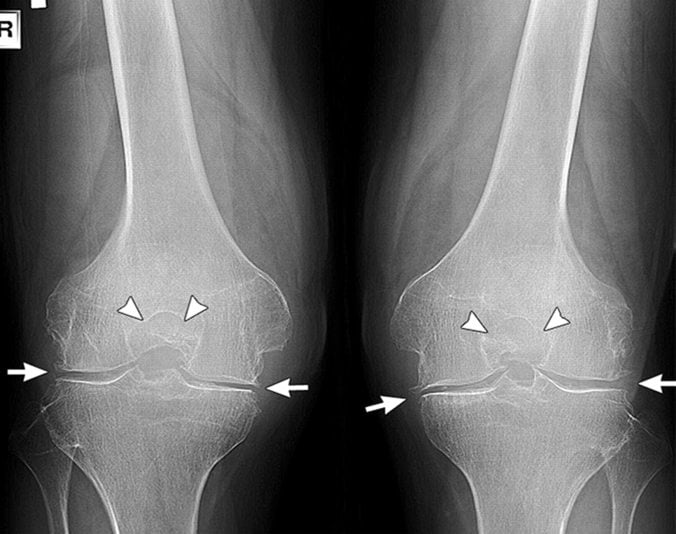

| Двухсторонний гонартроз 1 степени | Во время движений может наблюдаться не выраженная крепитация. Сам сустав еще не деформирован. Человек передвигается без вспомогательной опоры. На снимках рентгена врач может увидеть небольшое сужение в суставной щели. Двусторонний артроз коленного сустава 1 степени приводит к ощущению повышенной утомляемости в ногах |

| 2 степень | При переходе болезни во вторую степень человек ощущает первые боли (стартовые). При сгибании ног больной замечает скованность. На снимках рентгена, помимо сужения суставной щели, специалист может выявить костные остеофиты. Двусторонний гонартроз 2 степени приводит к атрофированию мышц бедра |

| 3 степень | Последняя стадия заболевания сопровождается постоянными болями, даже в ночное время. В очаге поражения возникает отечность. Нередка полная блокада сустава: больной не может сгибать или разгибать ногу. При осмотре врач отчетливо видит деформацию коленей |

- рентгенография пораженных суставов;